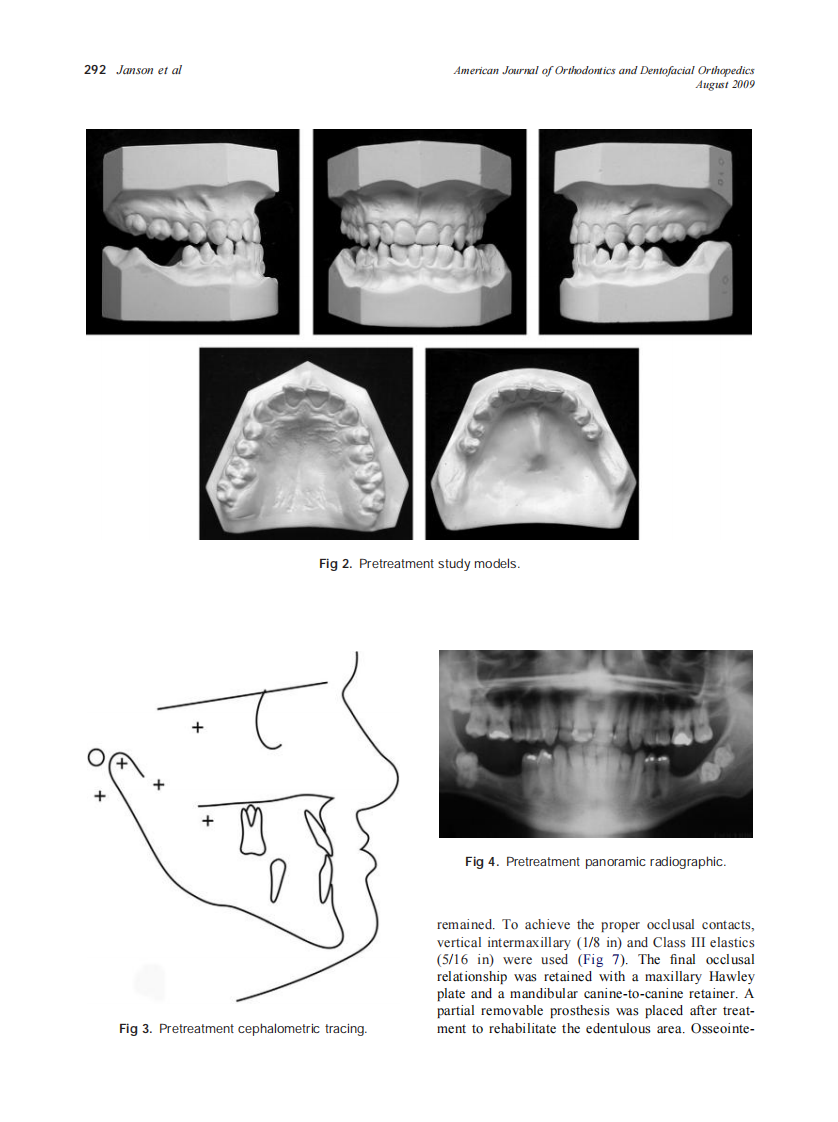

2009_136_2_290_298.pdf